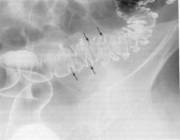

MEGACOLONUL CONGENITAL (BOALA HIRSCHPRUNG )

Megacolonul congenital reprezinta o dilatare marcata a colonului, cu exceptia rectului care are un calibru normal sau chiar redus. El este produs de absenta celulelor ganglionare ale plexului mienteric, care determina o întrerupere a peristalticii. Se poate asocia cu megavezica.

Radiografia simpla abdominala evidentiaza o distensie marcata a colonului cu aer si materii fecale. Diafragmele sunt ascensionate. Examenul cu bariu trebuie facut cu precautie datorita posibilelor accidente.